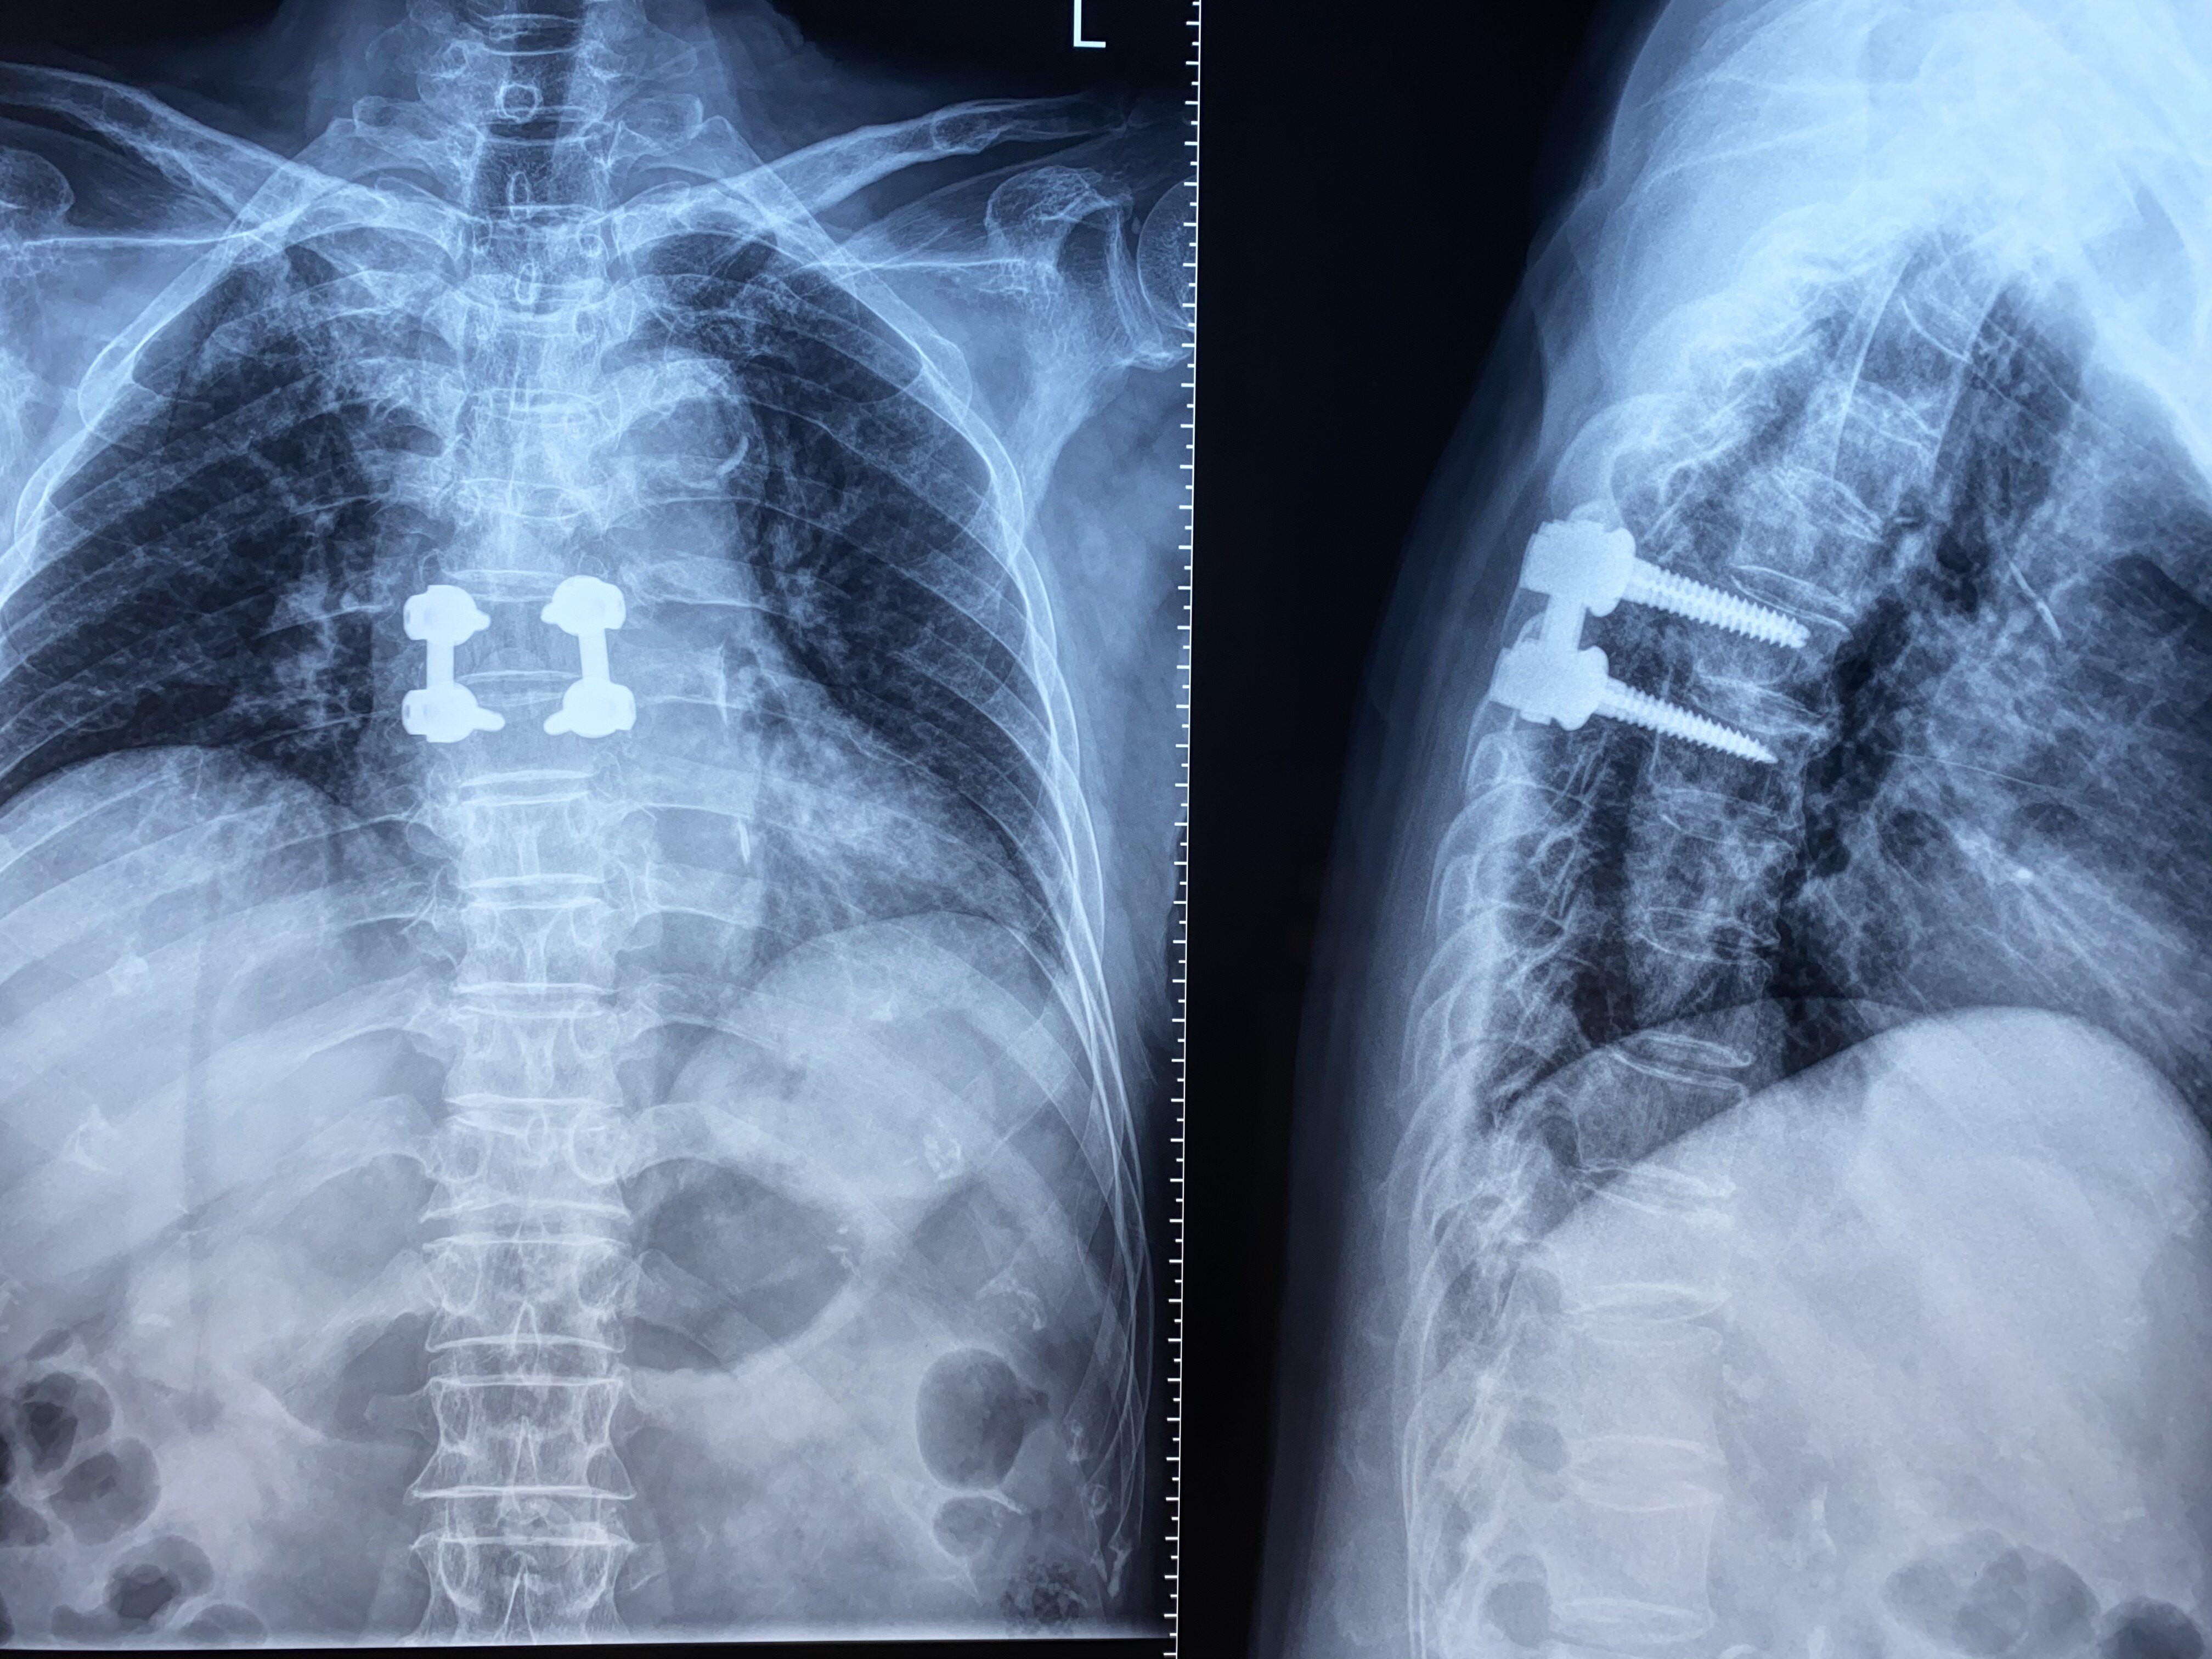

胸椎管内肿瘤完整摘除 - 好大夫在线

疫情下的救治系列:胸椎管内肿瘤